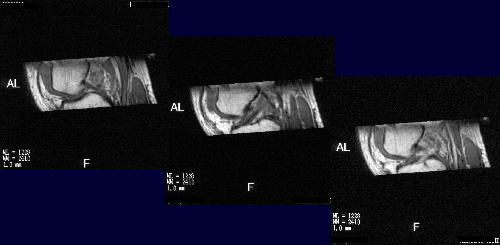

| 幚尡偦偺侾丗TI忦審専摙 丂僼傽儞僩儉傪嶣憸偟偰丄侾斣C/N偺椙偄嶣憸忦審傪専摙偟偨丅 丂丂丂丂丂丂丂  |

| 幚尡偦偺俁丗儃儔儞僥傿傾偱偺忦審専摙 丂丂丂丂丂丂丂丂丂丂嵟廔揑側嶣塭忦審 丂丂丂丂丂丂丂丂丂丂丂丂丂FSE3D10-12(Real-IR 3D) 丂丂丂丂丂丂丂丂丂丂丂丂丂TR/TE=800/10 TI=600 丂丂丂丂丂丂丂丂丂丂丂丂丂FA=90/180 丂丂丂丂丂丂丂丂丂丂丂丂丂NS=40 丂丂丂丂丂丂丂丂丂丂丂丂丂ST=1mm 丂丂丂丂丂丂丂丂丂丂丂丂丂FOV=15cm 丂丂丂丂丂丂丂丂丂丂丂丂丂Matrix=224*224 丂丂丂丂丂丂丂丂丂丂丂丂丂NAQ=1 丂丂丂丂丂丂丂丂丂丂丂丂丂Time=11min11sec 丂丂丂丂丂丂丂丂丂丂丂丂丂Fine Recon&Mid Slice傪巊梡 |